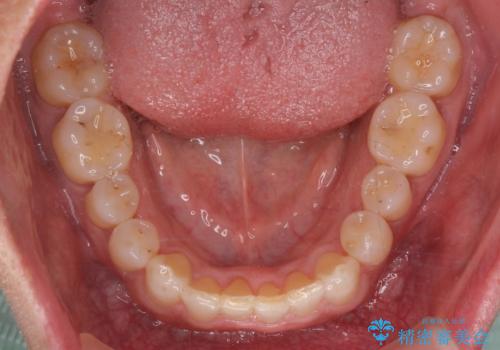

八重歯と下の歯のがたつき マウスピースで

- 右上の犬歯が目立つのが気になる、下の歯並びも治したいとのことで来院。

歯を抜かずに少し削って小さくして並べました。

並びも良くなり、患者様にも喜んでいただきました。

右上の犬歯の歯肉退縮自体は進行する可能性をお伝えしておりましたが、特に変化なく治療できました。